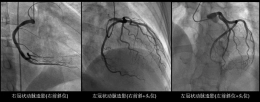

为加强医联体建设,进一步提升日照市康复医院医疗服务能力,9月11日,青岛心血管病医院与日照市康复医院医联体揭牌仪式暨学科发展共建交流会在我院举行。青岛心血管病医院党委书记、理事长李炯佾、青岛心血管病医...